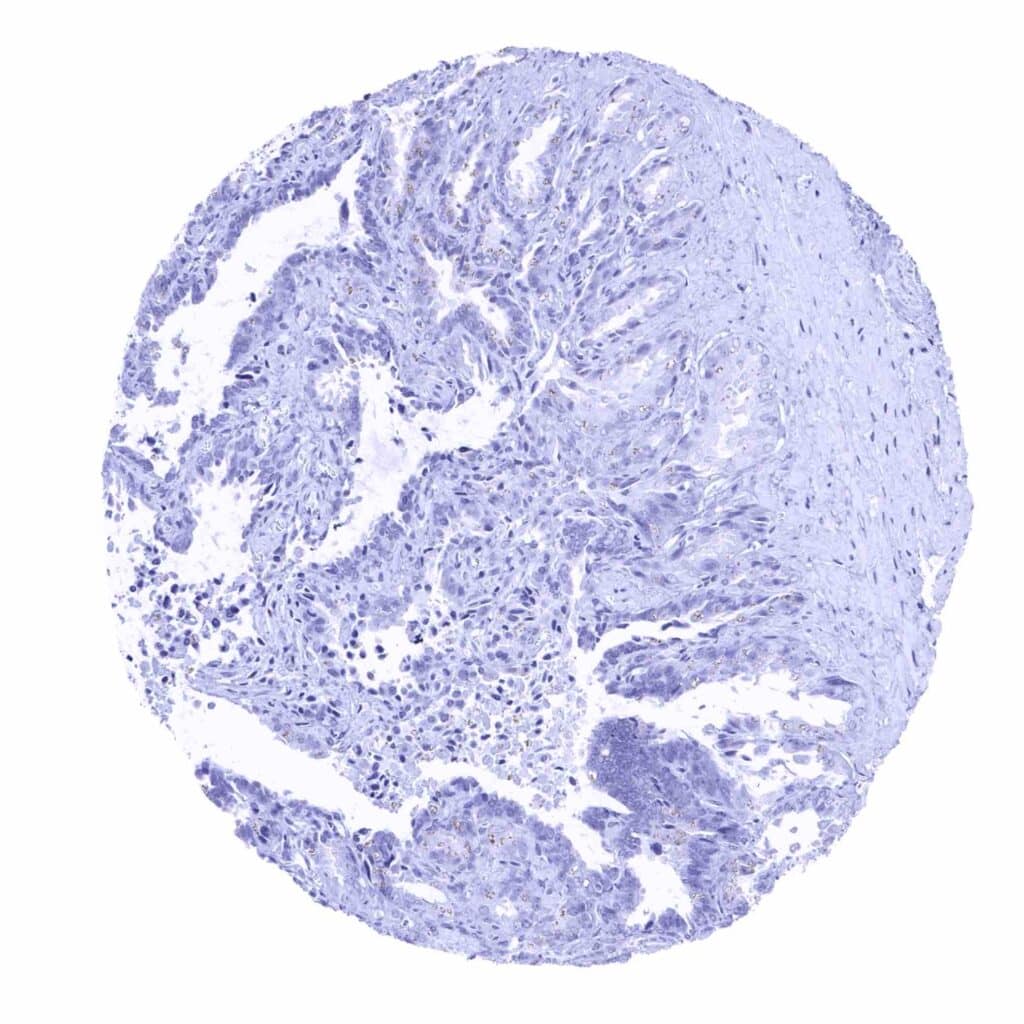

Prostate – Intense granular, cytoplasmic prostein staining of luminal cells of the prostate (prostein immunohistochemistry)

Prostate – Luminal epithelial cells of the prostate show a strong granular, perinuclear cytoplasmic prostein staining (prostein immunohistochemistry)

Prostate – Strong, granular, perinuclear cytoplasmic prostein staining of luminal cells of the prostate (prostein immunohistochemistry)